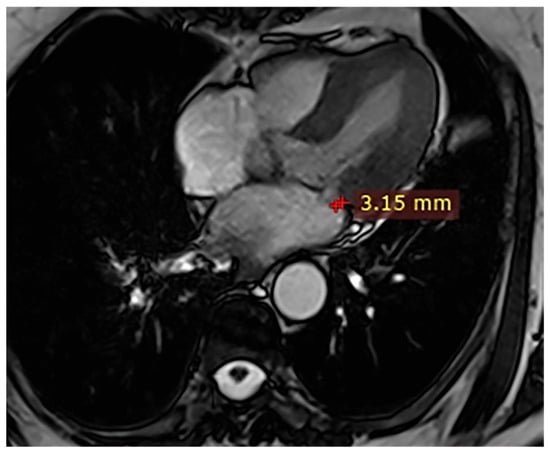

| 3 | Female, 74 years old | Extrasystole | 3 | - | No LGE | No LGE; patient reassured and scheduled for periodic clinical follow-up |

| 5 | Male, 63 years old | Heart failure | 2,5 | MVP, valvular regurgitation | No LGE | Reduced LVEF (47%) with left atrial dilatation; heart failure therapy optimized; follow-up planned. |

| 6 | Male, 68 years old | Palpitations | 5 | - | Lateral | LGE in basal lateral wall; electrophysiological evaluation and ECG monitoring recommended. |

| ≥1 mm (any measurable MAD) | Gupta et al. [1]; Troger et al. [2]; Figliozzi et al. [7]; Custódio et al. [13]; Zugwitz et al. [14]; Gulati et al. [11] | Large echocardiographic and CMR cohorts, including general populations and patients with mitral valve prolapse. | Using any measurable MAD (≥1 mm) as the definition leads to a very high reported prevalence in both general CMR cohorts and MVP populations, with high sensitivity for detecting any disjunction but limited specificity; many individuals with small MAD and no clear arrhythmic substrate are included. |

| ≥4 mm (moderate MAD) | Figliozzi et al. [7]; Perazzolo Marra et al. [15] | Consecutive CMR cohorts and arrhythmic mitral valve prolapse populations with systematic MAD measurements. | When MAD ≥ 4 mm is examined separately, its prevalence is markedly lower (around 10–15% in consecutive CMR series), and it shows a stronger association with structural abnormalities, non-ischemic LGE in basal lateral segments, and a higher burden of ventricular ectopy or ventricular tachycardia, particularly in arrhythmic MVP cohorts. This threshold has therefore been used as a more specific marker of potentially pathological MAD compared with very small disjunctions. |